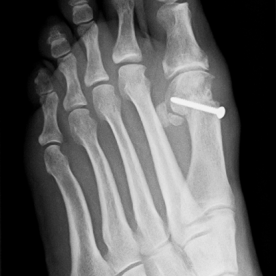

12) Hallux valgus

Häufigste und bedeutendste Zehendeformität mit seitlicher Abweichung der Großzehe im Grundgelenk. Es findet sich eine häufige Kombination mit einer Hammer- und Krallenzehe. Die konservative Therapie, meist im Frühstadium, umfasst die Druckentlastung des Großzehenballens, Barfußlaufen, ringförmige Schaumstoffpolster und Einlagenversorgung.

In fortgeschrittenen Fällen ist in der Regel eine operative Therapie mit Stellungskorrektur der Großzehe notwendig.

Röntgenbilder